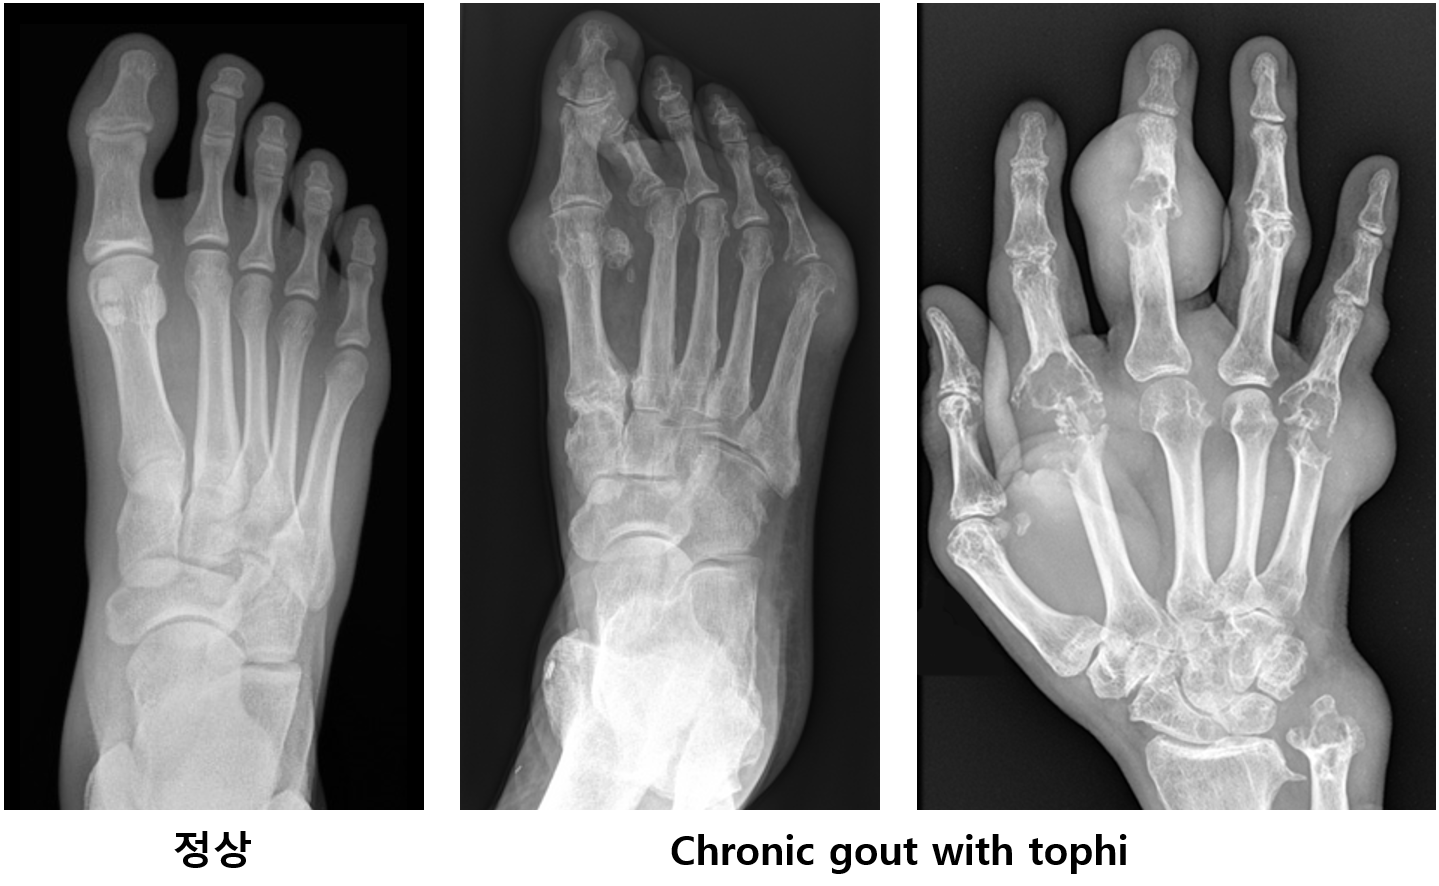

(2) Plain X-ray

(1) 질병 초기: 관절 붓기, soft tissue swelling

(2) 만성 통풍: Tophi, soft tissue swelling, cystic change, 경계가 뚜렷한 미란, 뼈 모서리의 경화, 연조직의 석회화 등